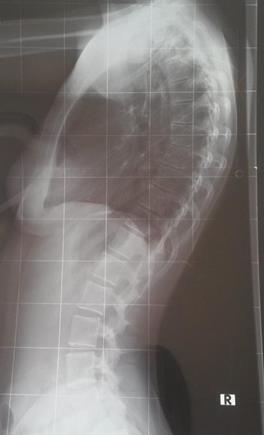

Soo ich melde mich noch einmal, da ich heute bei Dr. Hoffmann war..

Bin immer noch ein bisschen "geschockt" über das Ergebnis, dachte das es besser ausfaellt, hab es wohl zu lange verdraengt :rolleyes:

Es sind jetzt 61° Kyphose, 6° Skoliose und ein leichter Beckenschiefstand

Für den Beckenschiefstand habe ich Einlagen verschrieben bekommen; die leichte Skoliose kommt wohl durch den Ausgleich des schiefen Beckens zustande und sei wohl nicht weiter schlimm.

Zur Kyphose meinte Dr. Hoffmann, dass ich sei noch sehr beweglich sei und da ich bis jetzt auch keine Schmerzen habe meinte er, dass eine Theraphie nach Schroth erst einmal völlig ausreichend sei. Darum werde ich mich dann morgen auch sofort kümmern.

Zusatzlich meinte er, dass es wohl ein leichter (?) Scheuermann sei, was man wohl an den Wirbeln sieht..

Habe euch mal die Bilder angehaengt; wo sieht man das denn? War leider bei dem Termin selbst ziemlich durch den Wind durch die Diagnose und hab diverses vergessen zu fragen :rolleyes:

Und sieht man denn da jetzt auch eine Hyperlordose oder nur eine Hyperkyphose?

Allgemein kam es mir bei ihm so vor, als ob er der Meinung war, dass das nun wirklich nicht sonderlich schlimm sei.. ja da machen wir ein bisschen Krankengymnastik, da brauchen sie sich nicht in ein Korsett zwaengen, das wird dann schon wieder - so nach dem Motto. Liegt das daran, dass scheinbar noch alles ziemlich beweglich zu sein scheint? Weil nach so wenig hört sich 61° meiner Meinung nach jetzt nicht an, und das seitliche Röntgenbild find ich auch sehr gruselig :rolleyes:

Dateianhänge

1.jpg

1.jpg (18.25 KiB) 17969 mal betrachtet

2.jpg

2.jpg (23.35 KiB) 17969 mal betrachtet

Der Ausdruck "ein leichter Scheuermann" ist mir aus dem Mund von Dr. Hoffmann auch neu. Es gibt in der Umgangssprache den Begriff "ich habe einen Scheuermann" und dann mit dem Begriff "leicht" die Tatsache, dass der nicht so ausgeprägt sei, womit man in der Regel die dadurch entstandende Hyperkyphose/Hyperlordose bezüglich Winkel meint.

Das trifft hier aber nicht zu, sodass ich vermute, dass Dr. Hoffmann Keilwirbel meint, die es bei Dir wohl nicht gibt. Ein weiteres Merkmal für einen abgelaufenen Scheuermann sind die Schmorlschen Knötchen, die er wahrscheinlich im Röntgenbild gesehen hat. Für die eigentliche Behandlung sind aber nur Keilwirbel relvant, die eine Korrektur erschweren können.

Ich sehe da schon eine Hyperlordose (Hohlkreuz) als Ausgleich zur Hyperkyphose.